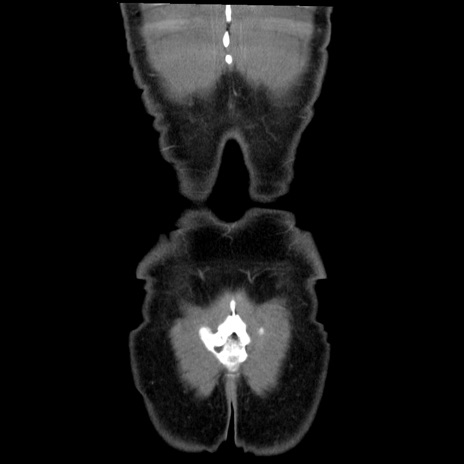

症例36(冠状断像)

【症例】20歳代 男性

【主訴】心窩部痛

【現病歴】今朝より上腹部痛あり。一旦軽快していたが再度出現したため救急要請。昨日夕に白身の魚を含む刺身を食べた。

【身体所見】BP 136/89mmHg、HR 74/min、BT 37.0℃、腹部:膨満、軟、心窩部に圧痛あり。反跳痛なし、筋性防御なし、腸雑音やや亢進あり。

【データ】WBC 17700、CRP 0.48